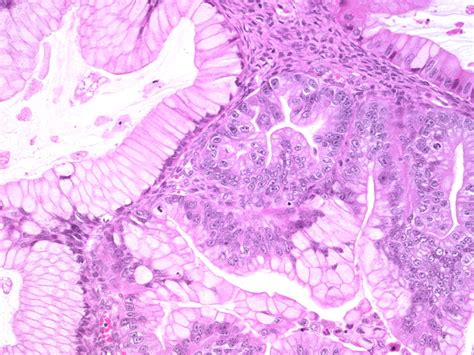

Tumor of low malignant potential,proliferative cystadenoma. Small borderline tumours do not usually cause symptoms, with the mass only being discovered during a test for something else. Evaluate the management of patients with borderline ovarian tumors. The positive prognosis is related to the fact that over 80% of cases are diagnosed at an early stage of the disease. What was labeled ovarian cancer in the past may really arise from fallopian tube. An introduction to the ovary is in the ovary article, which also deals benign cysts. The role of serous borderline ovarian tumors (bots) in the pathogenesis of serous ovarian carcinomas is unclear. A histopathological term that describes an ovarian tumor of low malignant potential that expresses cytologic features of malignancy without frank invasion.

Defined, nonobligate precursor to low. What was labeled ovarian cancer in the past may really arise from fallopian tube. Since bot were first identified >40 years ago. A borderline tumor, sometimes called low malignant potential (lmp) tumor, is a distinct but yet heterogeneous group of tumors defined by their histopathology as atypical epithelial proliferation without stromal invasion. Tumor of low malignant potential,proliferative cystadenoma. Serous borderline tumors — among ovarian borderline tumors, approximately 65 to 70 percent are serous histology, and borderline tumors account for an estimated 15 to 20 percent of all ovarian. The article examines ovarian tumours including ovarian cancer. The role of serous borderline ovarian tumors (bots) in the pathogenesis of serous ovarian carcinomas is unclear. Borderline ovarian tumours generally affect women of reproductive age. Borderline tumors of the ovary: Tumor of low malignant potential (lmp tumor). 6 abstracts with ovarian borderline tumors (bots) research. They are different to ovarian cancer because they don't grow into the supportive tissue of the ovary (the stroma).

The article examines ovarian tumours including ovarian cancer. Borderline ovarian tumours generally affect women of reproductive age. Serous borderline tumors — among ovarian borderline tumors, approximately 65 to 70 percent are serous histology, and borderline tumors account for an estimated 15 to 20 percent of all ovarian. Borderline ovarian tumours (bot), i.e., tumors with a potentially low level of malignancy, belong to a single category of epithelial new formations in the international hystological classification of who. Most borderline ovarian tumours are classified as serous from their appearance under the microscope.

What was labeled ovarian cancer in the past may really arise from fallopian tube. Tumor of low malignant potential,proliferative cystadenoma. Formulary drug information for this topic. A histopathological term that describes an ovarian tumor of low malignant potential that expresses cytologic features of malignancy without frank invasion. Small borderline tumours do not usually cause symptoms, with the mass only being discovered during a test for something else. Surgical management of borderline ovarian tumours. A retrospective study was conducted in 40 patients with borderline ovarian tumors treated between. Most borderline ovarian tumours are classified as serous from their appearance under the microscope.

Compared to invasive epithelial ovarian cancers, bot occurs more commonly at a younger age, during the time of. Borderline ovarian tumors are a type of epithelial ovarian tumors that exhibit some characteristics of malignancy, but appear to still be early enough in their development to be treated successfully. Borderline ovarian tumors (bot) are uncommon but not rare epithelial ovarian neoplasms, intermediate between benign and malignant categories. Most borderline ovarian tumours are classified as serous from their appearance under the microscope. Mdct and mri of borderline ovarian tumors original report nandita m. It was not until 1971 that the category. An introduction to the ovary is in the ovary article, which also deals benign cysts. They tend to develop in an exophytic growth pattern, on the surface of the ovary, without invading the underlying stroma. The role of serous borderline ovarian tumors (bots) in the pathogenesis of serous ovarian carcinomas is unclear. Borderline ovarian tumors (bots) are common in women in their reproductive years. Borderline ovarian tumours (bot), i.e., tumors with a potentially low level of malignancy, belong to a single category of epithelial new formations in the international hystological classification of who. Ten to fifteen percent of epithelial ovarian tumors are considered borderline malignancies. Serous borderline tumors — among ovarian borderline tumors, approximately 65 to 70 percent are serous histology, and borderline tumors account for an estimated 15 to 20 percent of all ovarian.